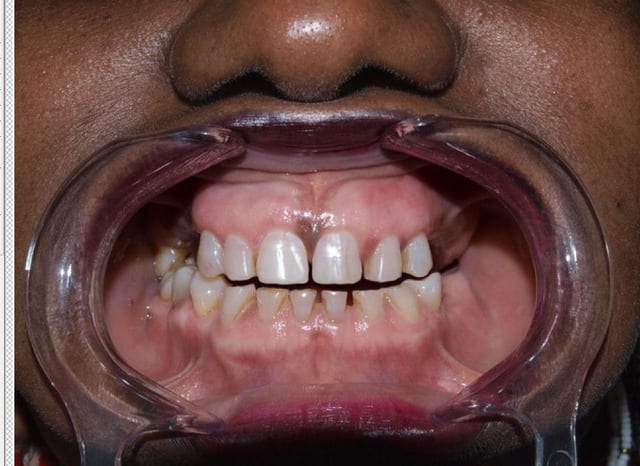

Photo interessante de simulation de l'epaisseur / longueur de materiau a rajouter

Fin ateqwa - Eugenol

Superposition epaisseur facettes couronnes hqyd8e - Eugenol